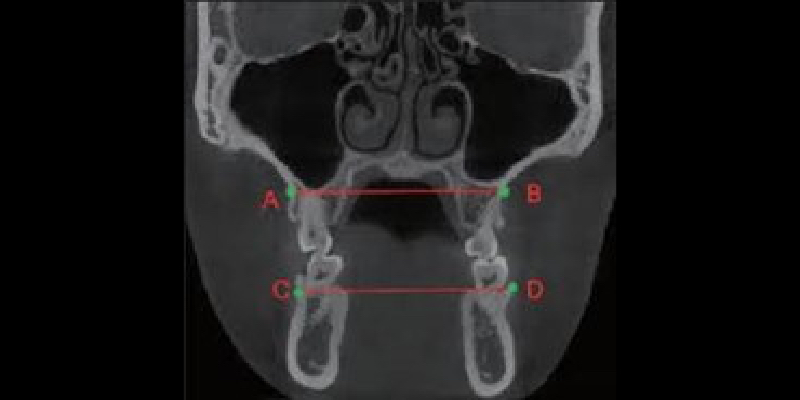

Transverse Dimension

The transverse dimension is also critical to visualize and understand, as deficiencies can result in sleep disorders, malocclusion, tooth wear, and improper growth. Practitioners can measure the maxilla and mandible to understand better their growth relationship (Fig. 7). The ideal relationship would be a measurement of maxilla plus 5.0 mm compared to the mandible. The image also demonstrates the patient’s inability to get their tongue to the palate.

How the tongue fills this space is an excellent indicator of narrow arches and a likely tongue-tie, which affected growth. Recognizing transverse dimension issues early can produce very predictable corrections through expansion. With the introduction of TAD expanders and surgical intervention, adults can correct these issues improving occlusion, sleep, and overall health.